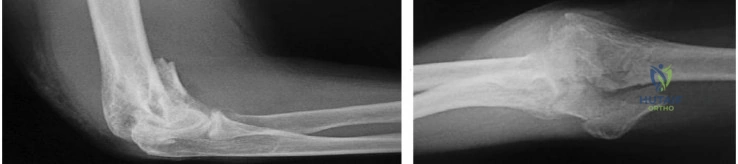

A 40-year-old male presents with a Terrible Triad injury of the elbow.

Surgical management is planned. What is the generally accepted sequence of repair to restore elbow stability?

A 45-year-old male sustains a 'terrible triad' injury of the elbow after a fall on an outstretched hand. Which of the following represents the most widely accepted sequence of surgical reconstruction to restore elbow stability?

Explanation

A 42-year-old female sustains a terrible triad injury of the elbow (elbow dislocation, radial head fracture, and coronoid fracture). During surgical reconstruction, what is the most appropriate standard sequence of repair?

Explanation

A 45-year-old female presents after a fall on an outstretched hand with a 'terrible triad' injury of the elbow. To properly restore elbow stability, what is the most widely accepted sequence of surgical repair?

Explanation